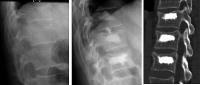

Abbildung 4: 3 Deckplatteneinbrüche am thorakolumbalen Übergang bei einem 40jährigen Patienten nach Sportunfall vor und nach Kyphoplastie

Keywords:

Fraktur

,

Kyphoplastie

Mineralstoffwechsel

Röntgenbild

Wirbelsäule